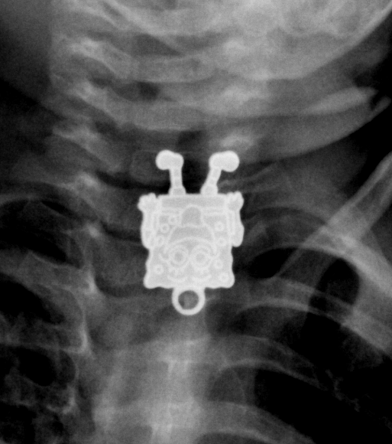

Wild X-Rays And Medical Photos